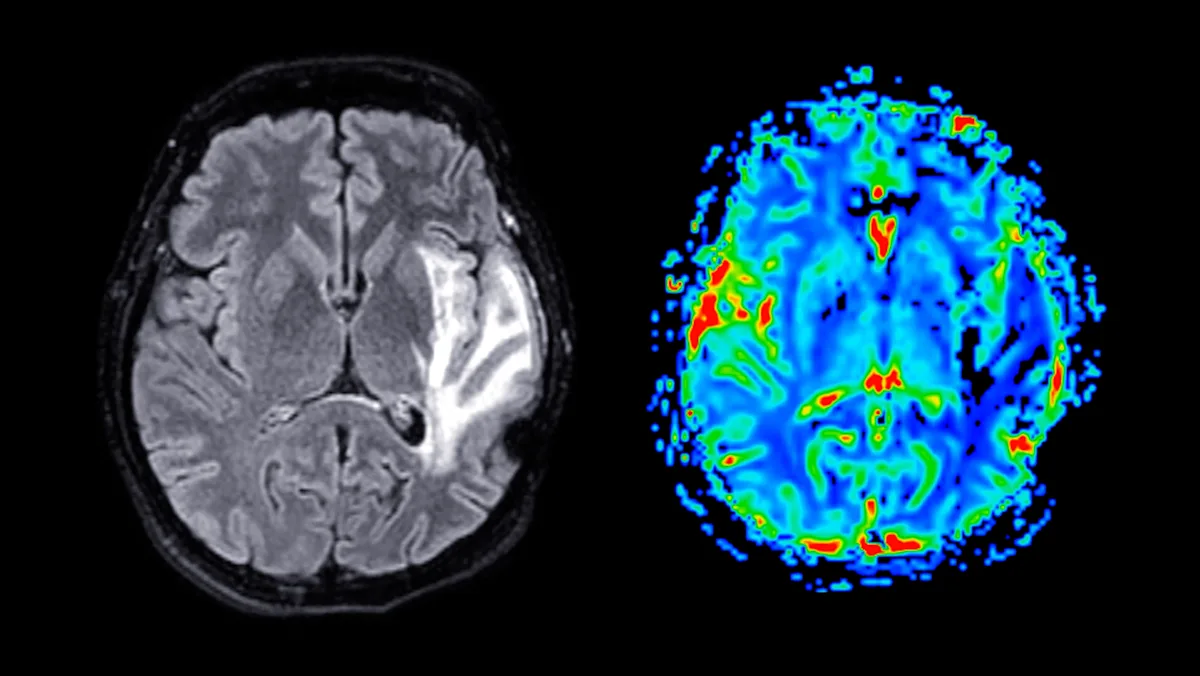

For years, scientists have understood the physical manifestations of Alzheimer’s disease. Research from the National Institute on Aging has identified sticky amyloid plaques, tangled tau proteins, and brain atrophy in Alzheimer’s patients.

The NMDAR/TRPM4 death complex also contributes to toxic signaling involving glutamate, which plays a role in the progression of Alzheimer’s. A study noted a clear increase in this complex within the brains of Alzheimer’s-affected mice—indicating a strong connection between brain health and the complex’s presence.